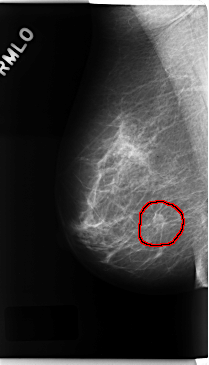

C_0225_1.RIGHT_MLO

RIGHT_MLO LINES 4736 PIXELS_PER_LINE 2712 BITS_PER_PIXEL 12 RESOLUTION 50 OVERLAY

FILE: C_0225_1.RIGHT_MLO.OVERLAY

TOTAL_ABNORMALITIES 1

ABNORMALITY 1

LESION_TYPE MASS SHAPE OVAL MARGINS SPICULATED

ASSESSMENT 5

SUBTLETY 5

PATHOLOGY MALIGNANT

TOTAL_OUTLINES 1

BOUNDARY